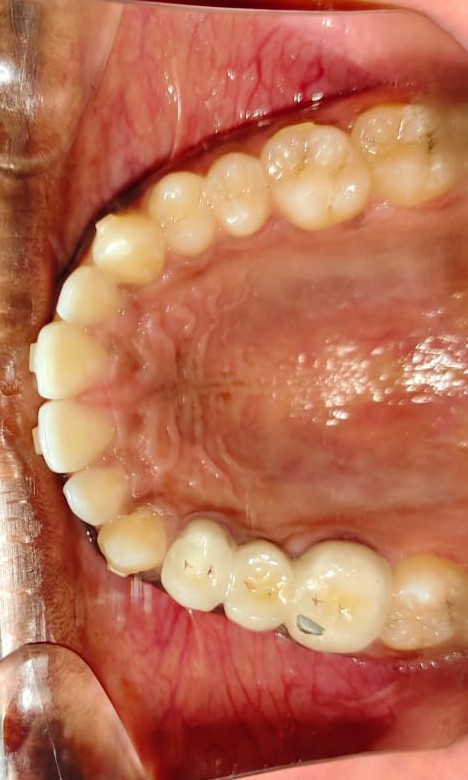

After/Before

See stunning smile transformation before and after

Before After